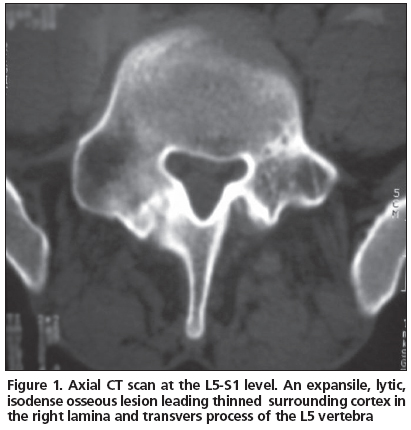

A 21 year-old male patient admitted to our clinic with low back pain persistent to medication for the last 3 years. He was first referred to physical medicine and rehabilitation department and then to a neurosurgery department after several visits because of persistent pain. He had no history of trauma. His pain was not aggravated by coughing, standing or sitting; and the pain was not relieved by salicylates or NSAIDs. Whole blood count (CBC), erythrocyte sedimentation rate (ESR) and rheumatoid factor (RF) were found within normal limits. Physical examinations were found normal except the tenderness extending from T12 to L5 associated with paravertebral muscle spasm. His lumbosacral CT was taken and then a tumoral mass was noticed enlarging transverse process and right lamina of L5 vertebrae with probable diagnosis of osteoblastoma or osteoid osteoma. The mass had a lytic nature with well defined osteosclerotic boundaries and facet joints were normal (Figure 1). An MRI was taken to evaluate the soft tissue expansion which showed no affection (Figure 2). A CT-guided biopsy resulted with unsatisfactory sample gathering. Then he has taken to the operation theatre and curettage and frozen section was performed since the probable diagnosis was osteoblastoma. After confirmation of benign tumoral process, the cavity was filled with allograft. The histopathological examination confirmed the diagnosis of osteoblastoma. Following surgery, the patient was asymptomatic; there was no neurological dysfunction and no residual pain or discomfort. No recurrence has been observed for four years.